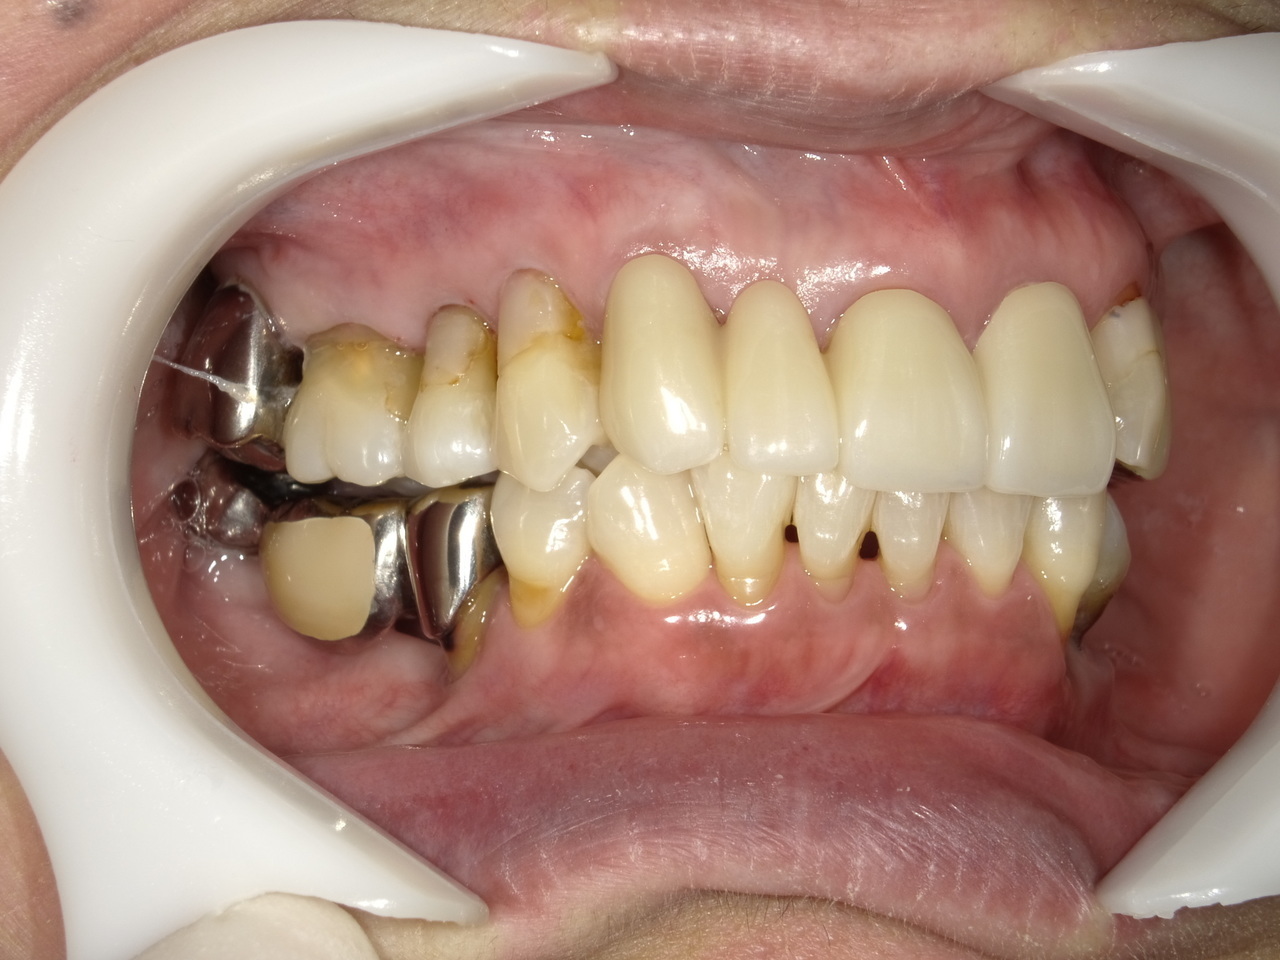

Before

枚方市のインプラントの症例

K・S様 女性 60代

症状としては、 右上4から7番までのすべての歯の著しい動揺があり、食事が困難であった。

治療法としては、患者様は、患者様が3か月以内の治療完了を望んでいたために、炎症が若干あったが、右上4から7番ぼすべての抜歯を行い、右上4番(抜歯即時埋入)、右上6番(上顎洞までの骨がほとんどないため、グラフトレスサイナスリフト施行)にインプラントを1回法で手術を終え、2か月半後にインプラントの状態が安定したために、3か月で上部構造の、右上456のジルコニアブリッジを装着して、治療を終えています。

治療結果としては、抜歯したと同時にインプラントを埋入することで、抜歯した穴が自然に治る過程で、インプラントの骨結合と組織の治癒が同時に行われるために、3か月という治療期間で治療を終了することができたことと、機能面・審美面でも回復を行うができた。また、右上6番に関しては、グラフトレスサイナスリフトを行うことで、従来のサイナスリフトに比べ、約9か月早く治療を終えることができました。

治療の期間・回数:約3か月、インプラント抜歯即時埋入から最終補綴物装着まで8回

治療の価格:792000円(税込)

治療費の内訳:インプラント基本料(フィックスチャー(メガジェンインプラントANYONE使用) 及び手術費用、投薬費用、レントゲン費用、インプラント上部費用(アバットメントおよびジルコニアクラウンの費用用)330000円×2 660000円(税込み)。オプション、抜歯即時埋入加算(人工骨費用を含まず)5500円×2 11000円(税込み)右上5ジル9コニアブリッジのポンテック費用 88000円 右上6グラフトレスサイナスリフト費用 33000円(税込み

治療のリスクや副作用:手術後に、痛みや腫れ、出血、合併症などを引き起こす可能性があります。噛む感覚がご自身の歯と異なる場合があります。見た目がご自身の歯と異なる場合があります。手術後にメインテナンスを継続しないと、インプラントが抜け落ちる可能性があります。